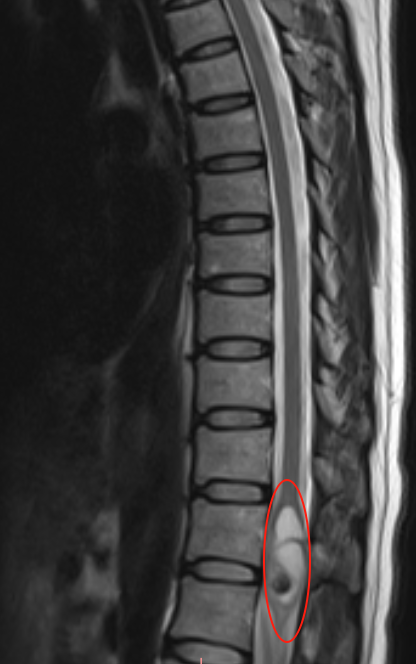

术前核磁检查报告

2年间反复腰痛,起初她并没有太在意。直到今年8月的一次飞行途中,飞机遭遇气流颠簸,剧烈的震动让她腰痛骤发,这次再也无法忽视。随后的核磁检查,发现T12髓内占位。多地求医,多位医生,说法各不相同:有笃定说手术没问题的,也有手术风险说的吓到人……